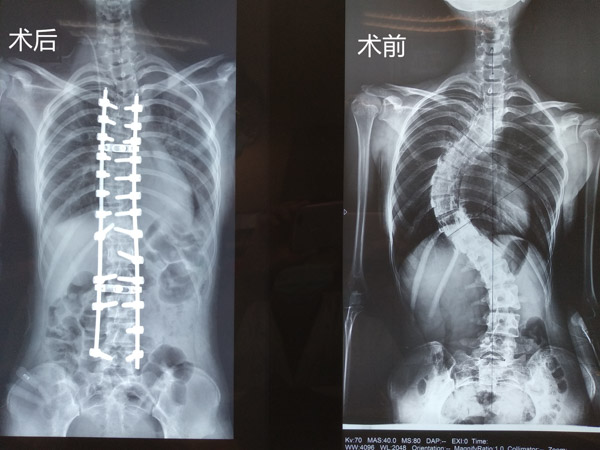

據我院脊柱外科主任胡朝暉介紹,小孔來院檢查時脊柱側凸畸形非常嚴重,已經對女孩的日常生活造成了嚴重影響,且畸形極可能進一步加重,壓迫心臟、肺、腹部等臟器,引起呼吸困難等心肺腹問題,還可能會出現頑固性背痛、站立和行走困難、跛行、肢體無力、大小便失禁等癥狀,必須通過手術對其脊柱側凸畸形進行矯形、固定。

“患者椎骨結構異常,椎體旋轉,椎弓根細小,均會導致術中置釘難度大大增加,且患者肺功能已受限,手術矯形后,兩肺空間重新分布,兩側胸腔大量積液會加重呼吸困難、甚至危及生命……”面對這一系列的困難,脊柱外科醫療團隊為小孔設計了多套應急預案,做好充分準備來應對可能出現的所有情況,確保手術萬無一失。

幾天后,脊柱外科醫療團隊頂著巨大的精神壓力為小孔進行脊柱側彎矯正術,術中置入26枚螺釘,歷時近7小時,手術非常成功,麻醉清醒后,小孔的雙腿可以自如活動,此刻包括胡朝暉主任在內的所有醫護人員都打心眼里為她高興。

術后恢復期,在脊柱外科護理團隊的精心呵護下,小孔的狀態一天比一天好,當她第一次下地活動,驚喜地發現自己的背竟然挺起來了!醫務人員告訴她,她足足長高了6公分!小孔激動得熱淚盈眶:我終于和其他同學一樣了,感謝各位叔叔阿姨!